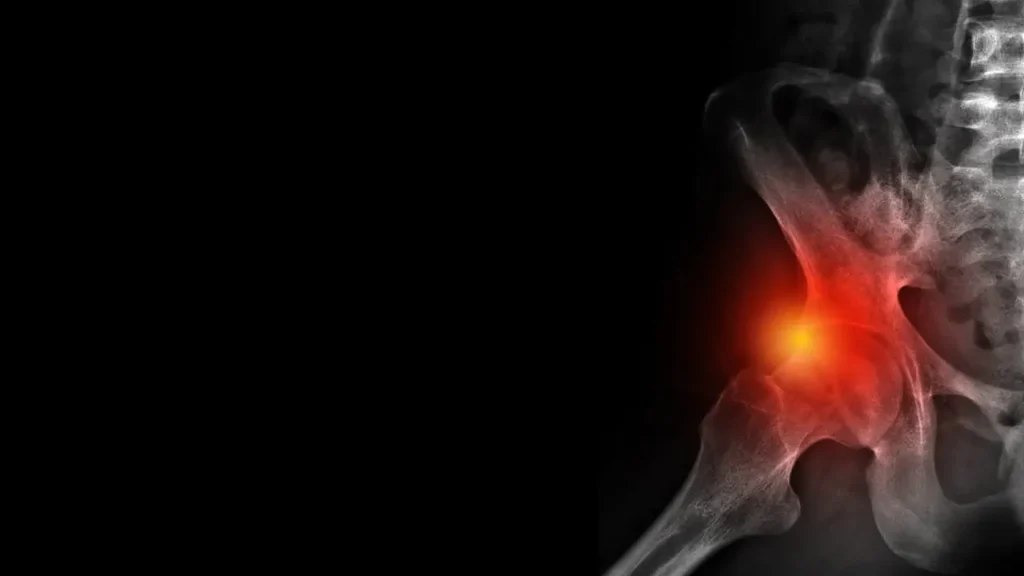

בית » אורטופד מומחה אגן וירך » תסמונת צביטה בירך

כאבים במפשעה, קושי בתנועה או תחושת ״תקיעה״ במפרק הירך הם תלונות שכיחות בקרב אנשים פעילים וספורטאים. במקרים רבים, הסיבה אינה עומס זמני אלא שינוי מבני במפרק עצמו. זיהוי מוקדם של הבעיה מאפשר טיפול נכון ומניעת נזק מצטבר למפרק הירך.

צביטה בירך (Femoroacetabular Impingement – FAI) היא מצב שבו מבנה לא תקין של עצם הירך או האגן גורם לחיכוך מוגבר במפרק, כאבים במפשעה ומגבלת תנועה. הטיפול מתמקד באבחון מדויק של סוג הצביטה ובהתאמת טיפול שמרני או ניתוח ארתרוסקופי (זעיר-פולשני), במטרה להפחית כאב ולמנוע פגיעה בסחוס.

צביטה בירך היא תסמונת הנגרמת עקב גדילה לא תקינה של אחת או שתי העצמות המרכיבות את מפרק הירך. כתוצאה מכך, בזמן תנועה רגילה, נוצר מגע לא תקין בין ״הכדור״ ל״סל״ של המפרק. החיכוך החוזר עלול לגרום עם הזמן לכאב, לפגיעה בסחוס ולנזק ללברום, טבעת הרקמה שמייצבת את המפרק.

משטחי המפרק מצופים סחוס חלק, המאפשר תנועה חופשית עם חיכוך מינימלי. סביב האצטבולום נמצאת טבעת הלברום, שתפקידה לייצב ולאטום את המפרק. בצביטה בירך, המגע הלא תקין פוגע קודם בלברום ובהמשך גם בסחוס.